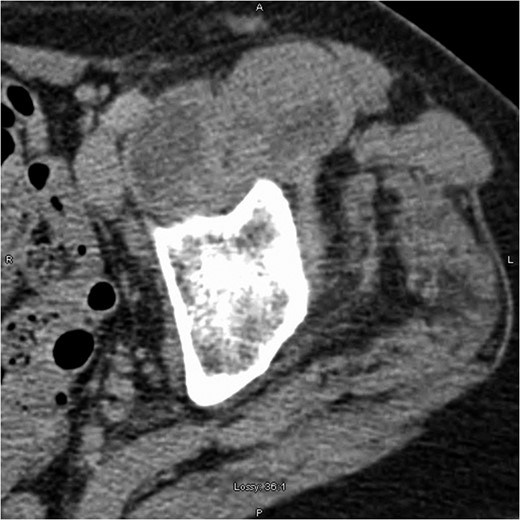

Computed tomography scan showing left iliopsoas involvement and heterogeneity, with a well-defined intramuscular hypoattenuation typical for abscess formation.